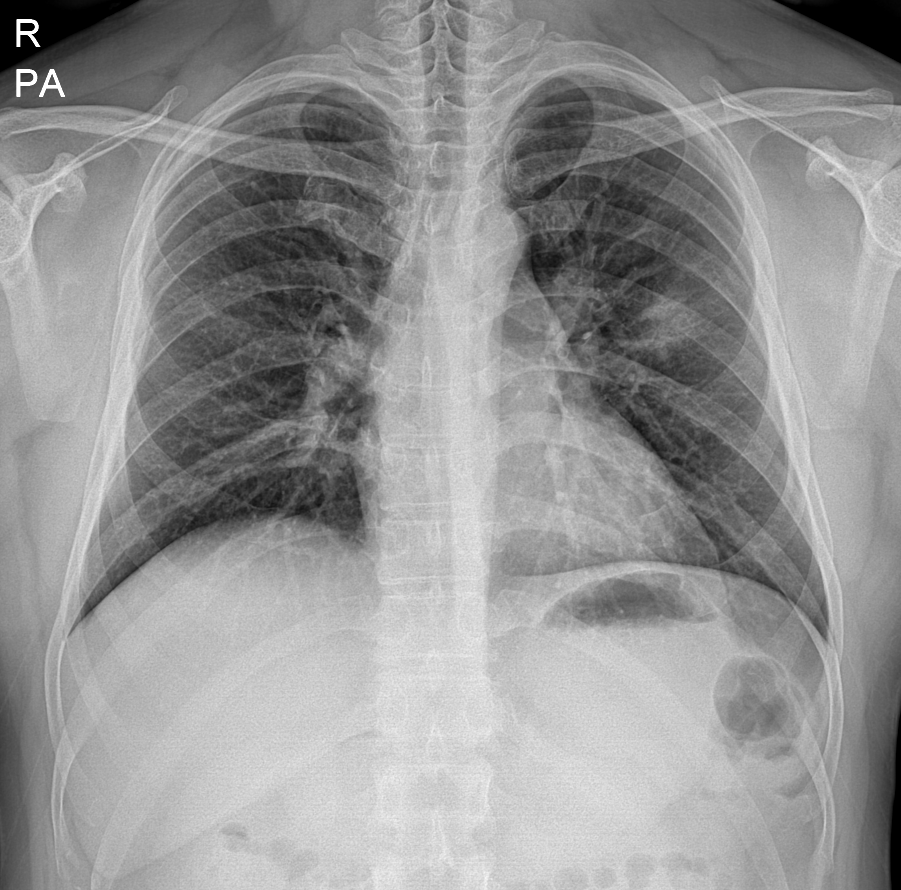

45세 남자

왼쪽부터 폐렴 진단 1년 전 흉부 엑스레이, 진단 당시 우상엽 폐렴